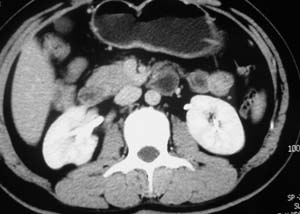

以下是引用子期在2010-3-19 20:47:00的发言:[br]血管畸形的ct增强应该有明显强化,本例并不相符合。本例双肾局部的略低密度影,累及肾盂,局部皮质明显变薄、内陷,增强扫描有轻度的强化,应考虑为炎性病变,患者为年轻男性,累及双肾的感染以结核较常见,可以没有明显的临床症状,尿中有时候也并不能查出什么;肾脓肿常有明显感染中毒症状,本例不符,另外一般的肾盂肾炎或肾小球肾炎通过小便就可确诊,其它还不能排除的是黄色肉芽肿性肾盂肾炎,然而单凭ct一般也很难鉴别。